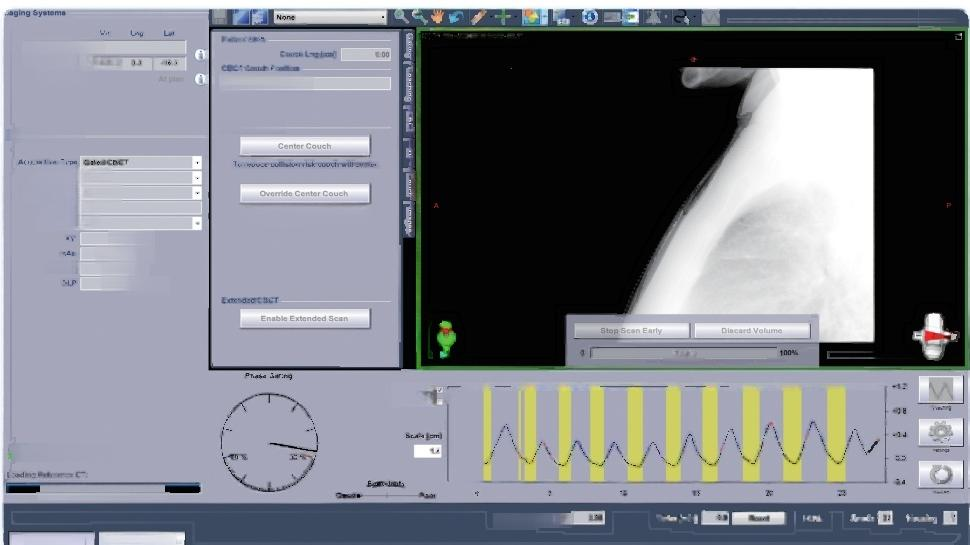

Respiratory gating radiotherapy technology

Respiratory gating radiotherapy technology can achieve more accurate irradiation by tracking pa- tient’s respiratory movement and accurately positioning the target,reducing the irradiation of normal tis- sues and reducing the side effects of radiotherapy.The main indications of this technology are lung,liver, breast,abdominal tumors and other tumors that are greatly affected by breathing.

Our first case of respiratory gating:May 11,2020